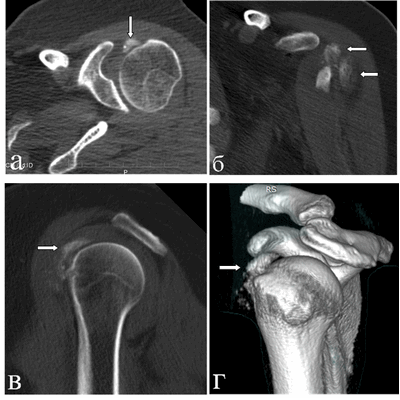

Результаты исследования и их обсуждение. При магнитно-резонансной томографии, (январь 2018 г.) в левом плечевом суставе выявлены умеренные дегенеративные изменения в виде краевых заострений суставной впадины лопатки, кальцинат в субдельтовидной сумке размерами 1,5х1,2 см, субхондральная киста акромиона диаметром до 0,4 см, небольшое количество выпота в субдельтовидно-субакромиальной сумке. Таким образом, МР-картина соответствовала акромиально-ключичному артрозу II стадии, плечелопаточному артрозу I стадии; выявлены субдельтовидно-субакромиальный бурсит, оссифицирующий капсулит плечевого сустава (рис. 1). Рекомендована консультация ортопеда.

Рис. 1. МРТ левого плечевого сустава пациентки Л., 49 лет (январь 2018 г.), Т1-ВИ, аксиальный срез (а) и Т2-ВИ, сагиттальный срез (б). В субдельтовидном пространстве в зоне отрога капсулы сустава вдоль сухожилия длинной головки на 9 часах условного циферблата головки плечевой кости визуализируется крупный кальцинат (обозначен стрелками) в виде гомогенно-гипоинтенсивного на Т1-ВИ и Т2-ВИ образования неправильно-округлой формы с четкими контурами размерами 1,5х1,2х1,1 см, без перифокального отека, деформирующий передний пучок дельтовидной мышцы

При компьютерной томографии выявлена диффузно-глыбчатая оссификация капсулы сустава по медиальной поверхности (на 8-12 часах условного циферблата головки плечевой кости по сагиттальным снимкам) на участке размерами 1,5х0,7х4,5 см плотностью от 200 до 890 HU (средней плотностью ~ 300 HU), медиальных отделов субдельтовидной сумки, в зоне малого бугорка (в области фиксации сухожилия подлопаточной мышцы), более «нежная» по капсуле вокруг вертикального сегмента сухожилия длинной головки бицепса; отсутствует в области фиксации остальных сухожилий ротаторной манжеты к большому бугорку и в самом сухожилии длинной головки бицепса (рис. 3). Данный характер оссификации также подтверждает представления о фазном характере течения рассматриваемой патологии.

Рис. 3. КТ левого плечевого сустава пациентки Л., 50 лет (март 2019 г.). Аксиальный срез (а) на уровне верхней части головки плечевой кости: бобовидной формы крупный кальцинат по медиальному контуру головки плечевой кости в зоне расположения капсулы; МПР-корональный срез демонстрирует расположение кальцинатов по капсуле вдоль вертикального сегмента сухожилия длинной головки бицепса (б), МПР-сагиттальный срез весьма наглядно показывает локализацию кальцинатов по капсуле и в зоне субдельтовидной сумки (в) и 3D реконструкция правого плечевого сустава в объемном представлении детализирует патологическое состояние в мягкотканых структурах сустава (г). Визуализируется оссификация капсулы вокруг сухожилия бицепса; кальцинаты в подклювовидном и субдельтовидном пространствах